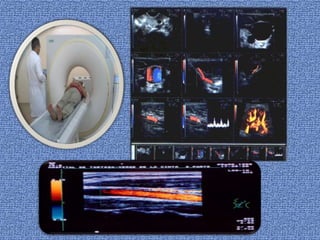

Exámenes

Exámenes Doppler, que usan ultrasonido u ondas

sonoras.

Arteriografía por resonancia magnética (ARM), un tipo

especial de resonancia magnética.

Tomografía computarizada especial llamada angiografía

por TC.

Arteriografía o angiografía, que utilizan rayos X para ver

dentro de las arterias.

Exámenes Exámenes Doppler, queusan ultrasonido u ondas sonoras. Arteriografía por resonancia magnética (ARM), un tipo especial de resonancia magnética. Tomografía computarizada especial llamada angiografía por TC. Arteriografía o angiografía, que utilizan rayos X para ver dentro de las arterias.